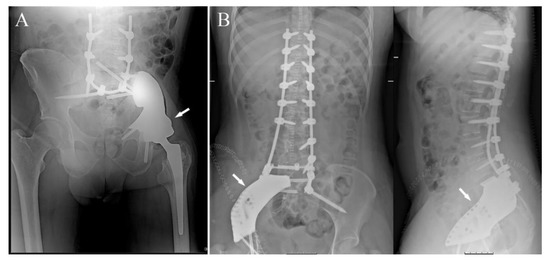

- The pelvic ring restoration: several authors sustain the importance of restoring the connection between the sacrum-iliac area, the acetabulum and the symphysis [25,26]; other authors sustain a non-anatomical reconstruction [26,27]. Connection to the symphysis could be a more stable fixation at first (Figure 7B), but in the long term, this technique could increase the risk of osteolysis in the symphysis (Figure 7C) (case 3) and prosthesis loosening. Indeed, a connection with the symphysis can transfer the stress forces to the bone–prosthesis interface at the acetabular level every time that weight-bearing is on the contralateral side; contrariwise, when weight-bearing is on the side of the prosthesis, the stress forces are transmitted to the prosthesis–bone symphysis interface with hypothetical easier mobilization. Based on these concepts, connection to the symphysis has to be well evaluated; actually, a fascia lata allograft can be used to reconstruct the inguinal ligament and support the abdominal viscera when necessary (Figure 7C). The fascia lata also decreases the friction between the vessels and the prosthesis and therefore the risk of their damage, as happened in one case of our series, in which the patient died from iliac vein rupture (case 5). Instead, reconstruction of the ileo-pubic ramus has an important biomechanical value; indeed, it represents a fulcrum with the iliopsoas muscle, allowing it to act as a hip flexor; when the ileo-pubic ramus is not reconstructed, the iliopsoas collapses inside the pelvis, acting more as an adductor muscle, with a consequent loss of flexion activity. Based on these considerations, while symphysis fixation presents a rationale, ischium fixation is not recommended because it would transmit cutting forces to the bone–prosthesis interface every time the patient sits down.When the tumor also involves the Enneking and Dunham T1 and 4 areas, spine stabilization is suggested to neutralize the cutting forces that act on the prosthesis (Figure 4A,B); in these cases, a median incision is completed to perform a bilateral stabilization; bone fusion is suggested to decrease the risk of pedicle screw loosening. This surgical step can be performed during tumor removal surgery or in a second moment to decrease the impact of a massive surgery on the patient. Actually, spine stabilization could become unnecessary in the future if osteointegration improves. A possible solution to improve osteointegration could be the use of a composite prosthesis composed by a 3DPTCMP as a scaffold for a vascularized autologous bone graft as a fibular flap; in that case, the 3DPTCMP should assure primary stability, whereas the fibular flap should give osteointegration and stability without the need of spine stabilization. Recently, Lu et al. proposed a similar composite structure for diaphyseal reconstruction after bone tumor removal with good results; actually, that technique could also be suggested for reconstruction in the Enneking and Dunham T 1 and 4 areas when the acetabular roof is spared [28].